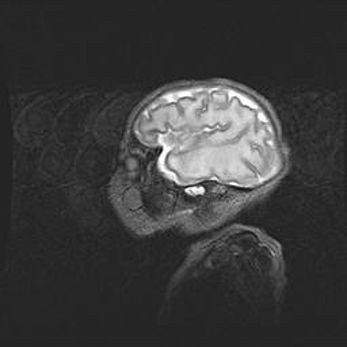

Множественные кисты обоих полушарий головного мозга, наибольшая из них в правой затылочной области. Ассиметричная атрофическая гидроцефалия.

Возраст: 7 месяцев

Вес: 5660 г

Пол: мужской

Окружность головы: 41,5 см

Срок гестации: 28-29 недель

Кисты головного мозга развиваются в результате многоочаговых некрозов вещества мозга и возникают вследствие перенесенной перинатальной инфекции, менингитов, энцефалитов, асфиксии, родовой травмы, расстройств мозгового кровообращения различного генеза. Образованию кист в веществе головного мозга плодов и новорожденных способствуют такие факторы, как высокое содержание в нем воды, недостаточная (или отсутствие) миелинизация и слабая астроглиальная реакция на повреждение.

Кисты могут сочетаться с гидроцефалией и другими поражениями головного мозга.